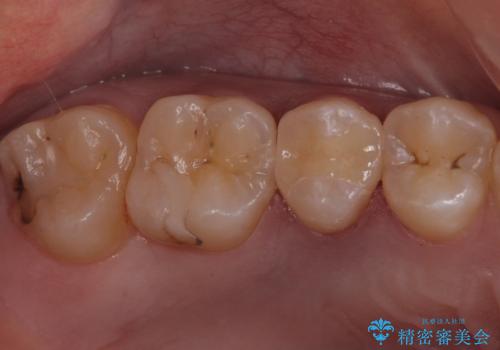

- 右上5 セラミックインレー 77000円×1本費用は治療当時の料金となります

外からも確認できる虫歯だけでなく、歯の奥の面の虫歯も残さず除去しました。

残った歯の量が多かったためインレータイプでの修復となりました。